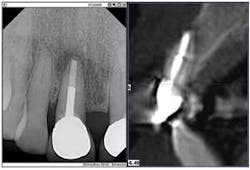

My intraoral X-ray (DEXIS) and cone beam (Gendex GXCB-500) systems often work together as my “dynamic duo.” While this scenario happens frequently, one example is a 66-year-old, retired teacher who reported a “funny feeling” in a front tooth (No. 8), but had no swelling or pain.

The enhanced digital X-ray, the first part of my duo, indicated radiolucency and a mid-root lesion in a tooth that already had a root canal and a post. It was apparent that the patient was headed toward an implant. But I had another tool that could tell us the extent of the destruction.

Here's where the second part of the duo, my CBCT system, came to my rescue. The 3-D image provided the further evidence of a horizontal root fracture.